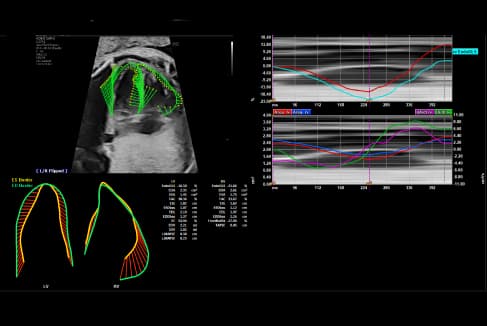

- 4D STIC Fetal echocardiography and Fetal Quantification ( fetal HQ analysis)

- Most advanced technology- including Voluson Expert 22 Ultrasound equipment with its full array of transducers and fetal HQ software- for fetal heart function assessment.

- Accurate diagnosis of fetal heart defects through real-time and offline analysis of fetal heart function evaluations.